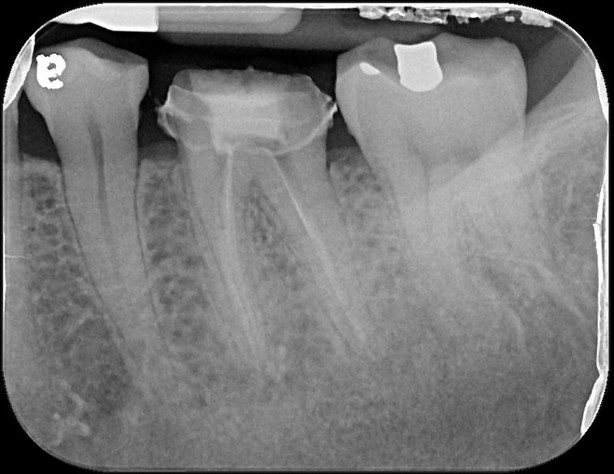

治療前,根管治療不完全

根管重治療與充填